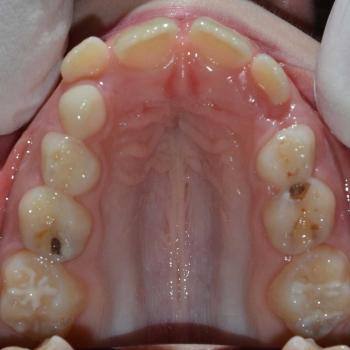

Csenge és édesanyja még vegyesfogazati időszakban, az egyetemen kerestek fel többszörös funkciós és esztétikai problémák miatt. Az első vizsgálat alkalmával súlyos nyitottharapást, keresztharapást, középvonal eltolódást, Angle II. osztályú eltérést, nyelvlökéses nyelést, helyhiányt diagnosztizáltunk, illetve elképesztő ritkaságként felcserélődött szemfog-kisőrlő csírákat találtunk a jobb oldalon.

Az eltérések mennyiségéből és súlyosságából fakadóan kizárólag többlépcsős kezelés jöhetett szóba, mely logopédiai kezelést, nyelvlökésgátló rácsot tartalmazó kivehető fogszabályozót, HYRAX készüléket, headgear-t, intermaxilláris gumikat és hagyományos fém fogszabályozót is igénybe vett.